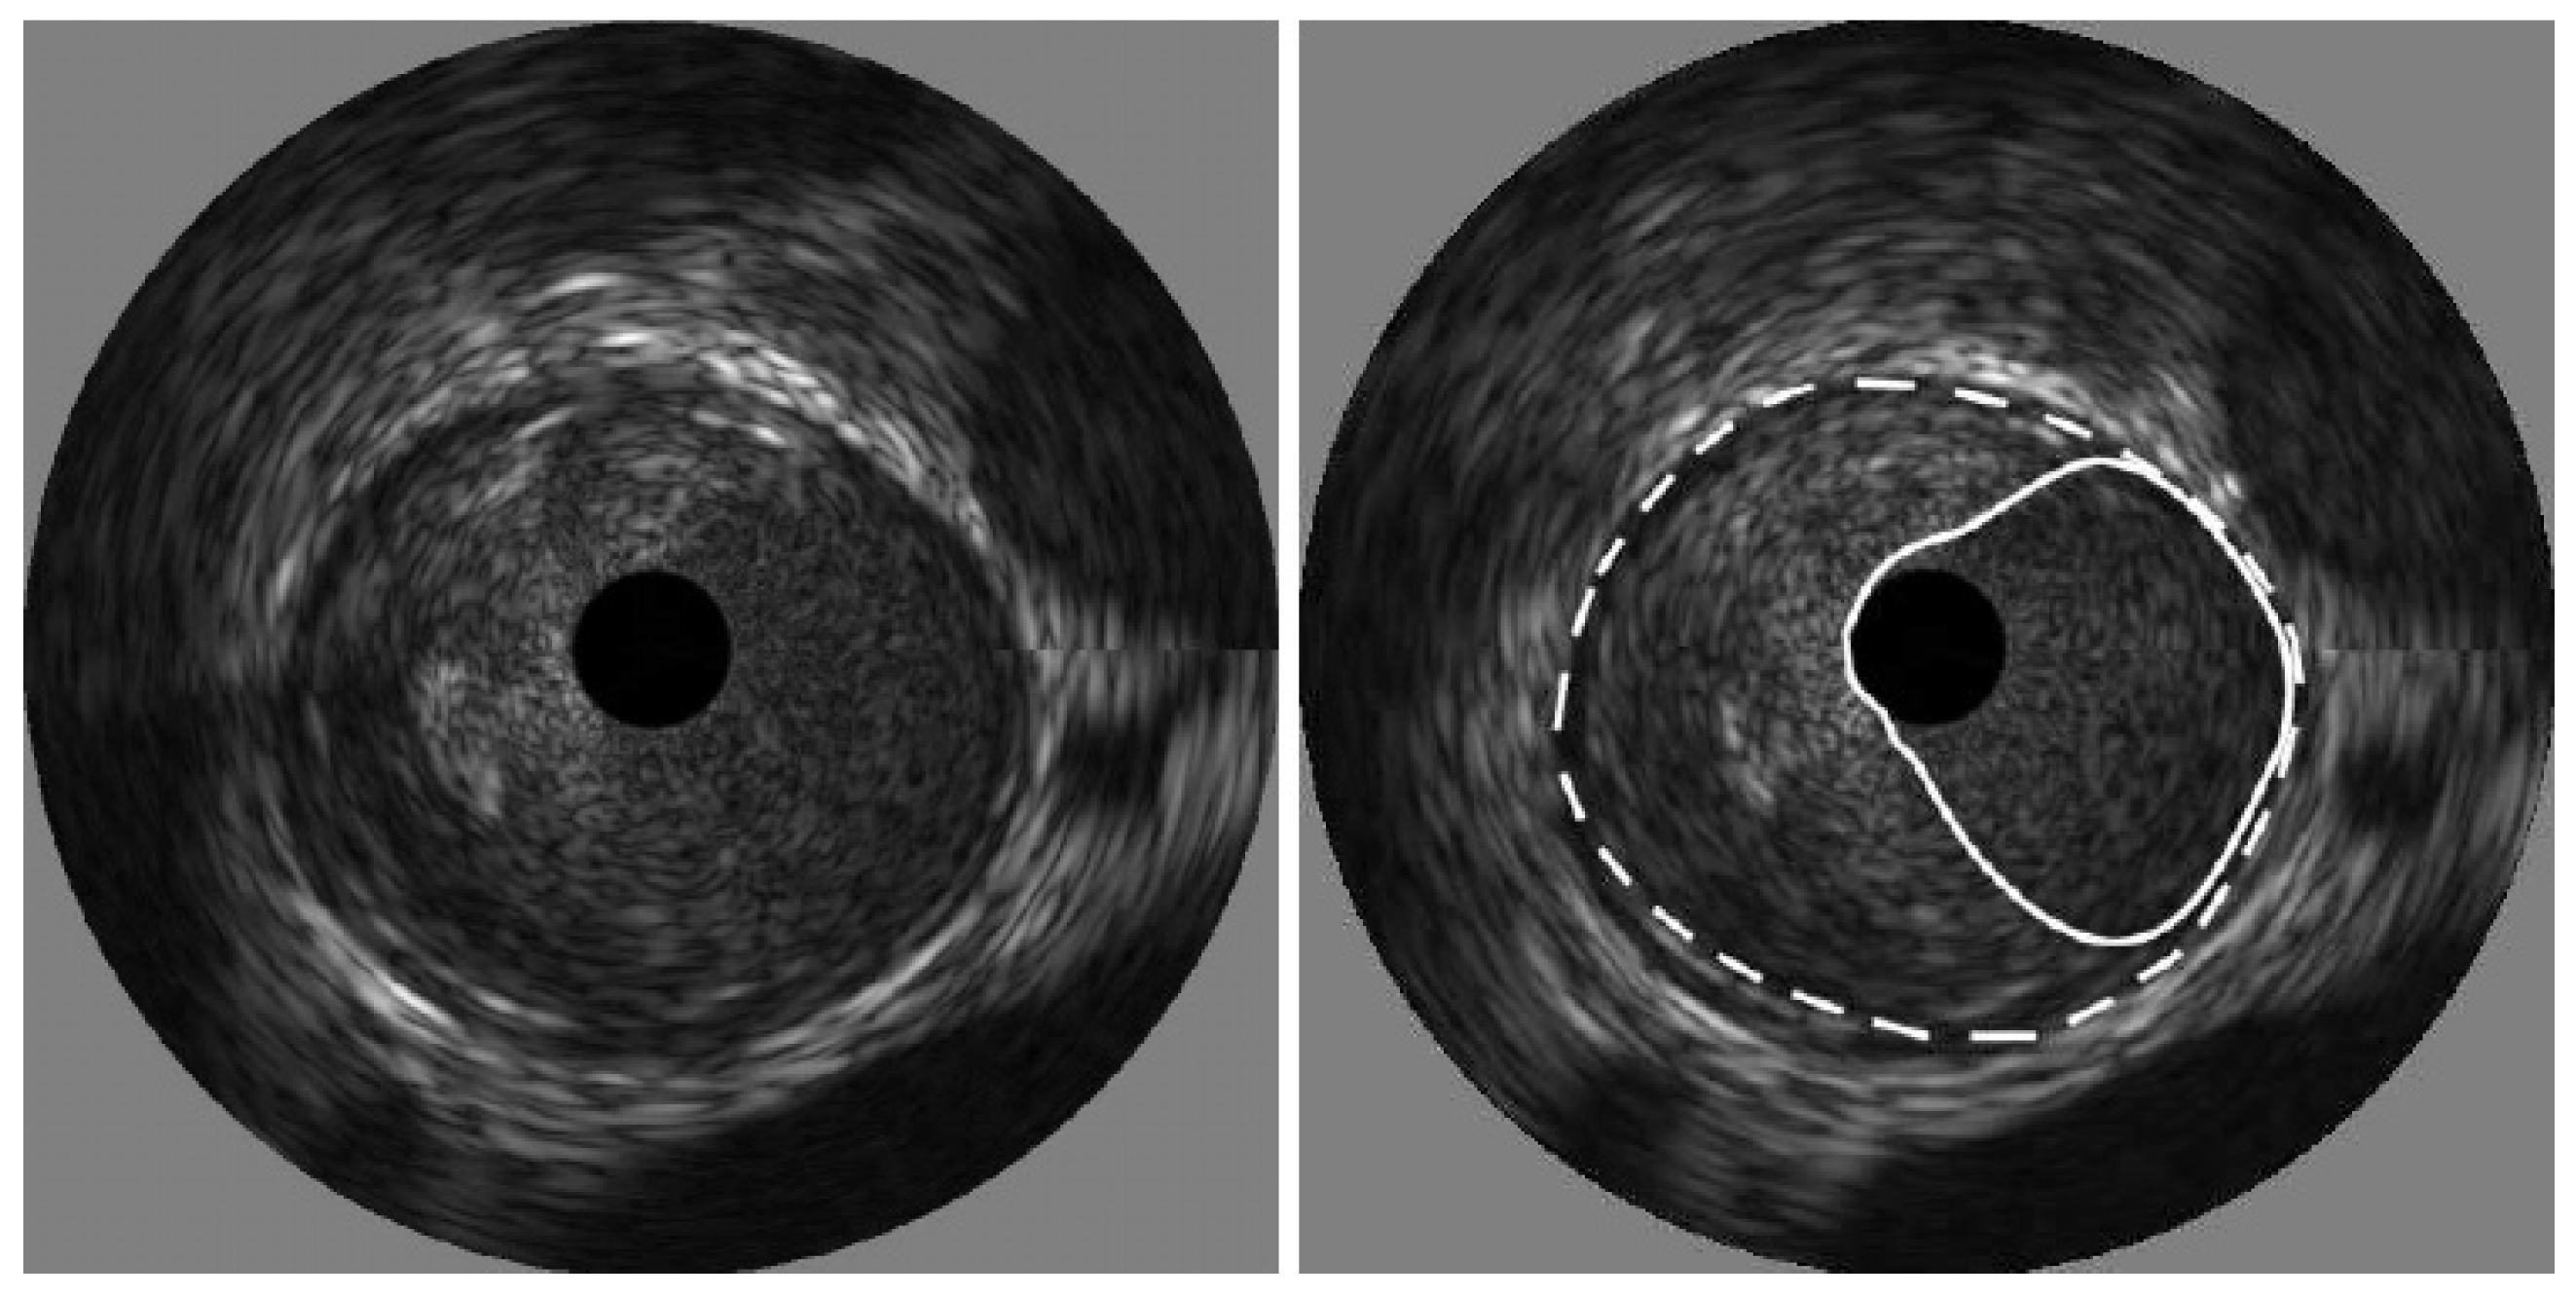

- Destrempes, F.; Cardinal, M.-H.R.; Allard, L.; Tardif, J.-C.; Cloutier, G. Segmentation method of intravascular ultrasound images of human coronary arteries. Comput. Med. Imaging Graph. 2014, 38, 91–103. [Google Scholar] [CrossRef]

- Kermani, A.; Ayatollahi, A. A new nonparametric statistical approach to detect lumen and Media-Adventitia borders in intravascular ultrasound frames. Comput. Biol. Med. 2018, 104, 10–28. [Google Scholar] [PubMed]